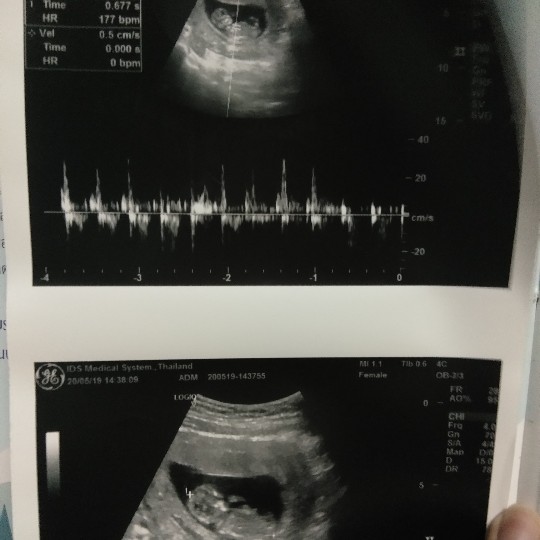

ของเราภาพตอน 12wค่ะ